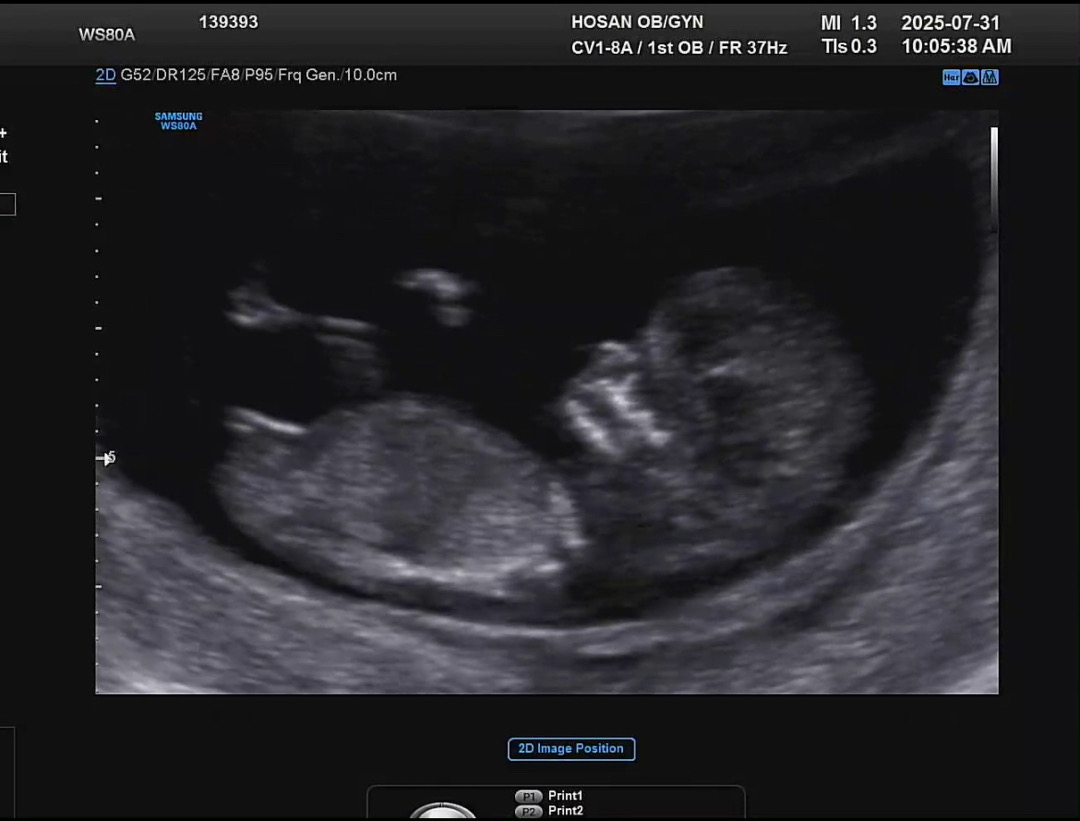

11주3일 각도법 성별 궁금해요!! 같이 봐주세요

병원에서는 아직 잘 모르겠다고 하시네요 ㅠㅠ